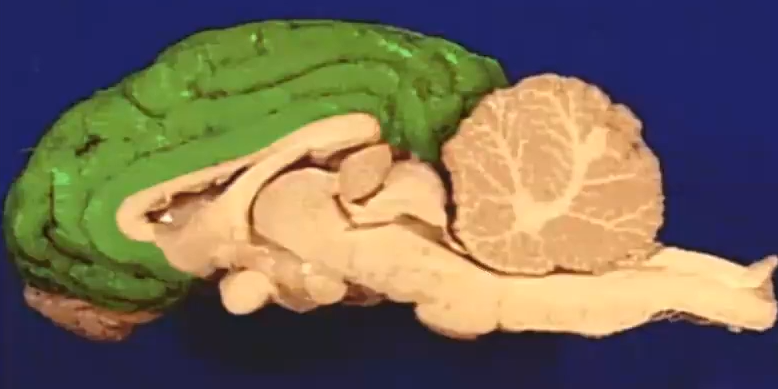

Name of Ridges Depression

Cerebral cortex

Coordinate language, thought, decision

“Grey matter”

Ridges: Gyrus

Depression: Sulcus

Name

Corpus callosum

Lobe Name

Frontal Lobe

Lobe

Temporal Lobe

Name

Thalamus

Lobe

Occipital Lobe

Lobe name

Parietal lobe

Name

Hypothalamus

What + (Two halves)

Midbrain

Superior Colliculi (Function not needed to remember)

Inferior Colliculi

Name+ inside (not asking for lobe name)

Cerebellum

Has arbor vitae inside, sensory motor information

Name

Pons

What is the nerve on the red dot

Olfactory bulb

Name

Medulla Oblangata

What nerve

Optic Nerve

Optic Chiasma

Right side is processed by left cerebral hemisphere

Name

Pineal Body

What produces releasing/inhibiting hormones

hypothalamus

Name + Function of two halves

Pituitary